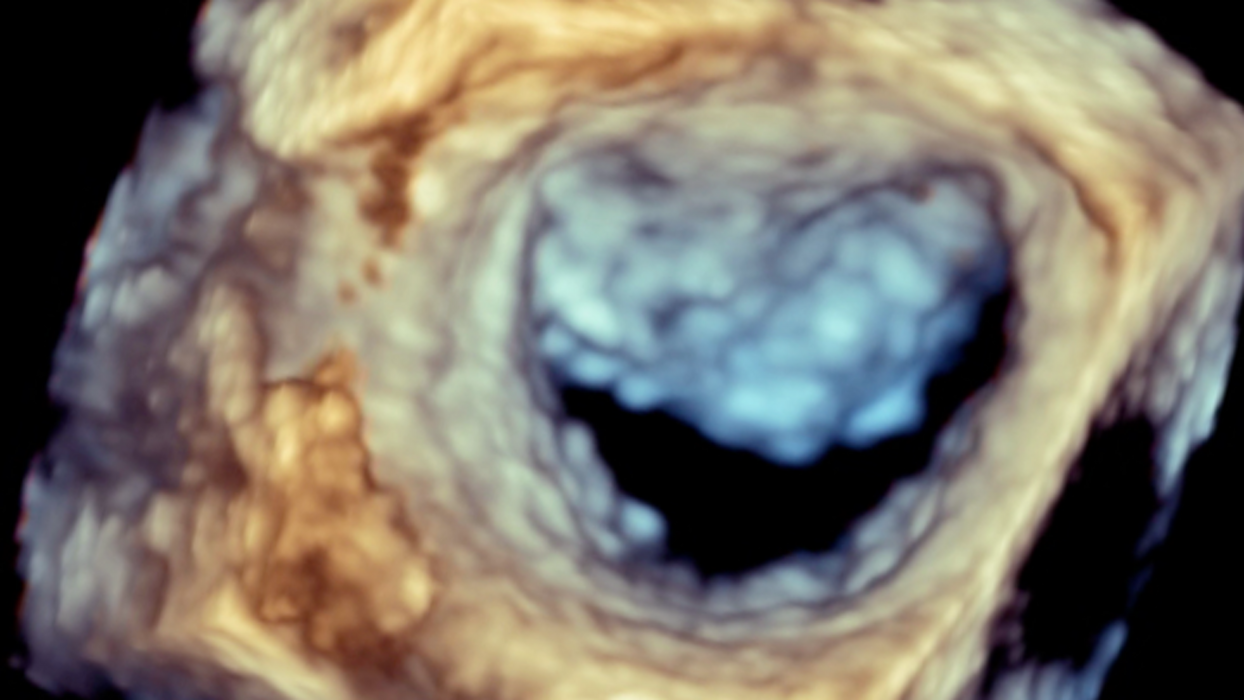

le quattro valvole del cuore, quali sono i sintomi, quali esami servono per studiarle,

una valvola importante che può essere curata in modi diversi